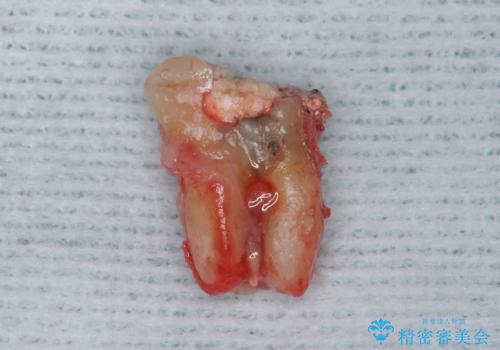

- 上顎の前から2番目の歯の古い樹脂をセラミックにしたいといらっしゃった方の症例です。

古い樹脂を除去後、オールセラミッククラウンによる補綴を行いました。